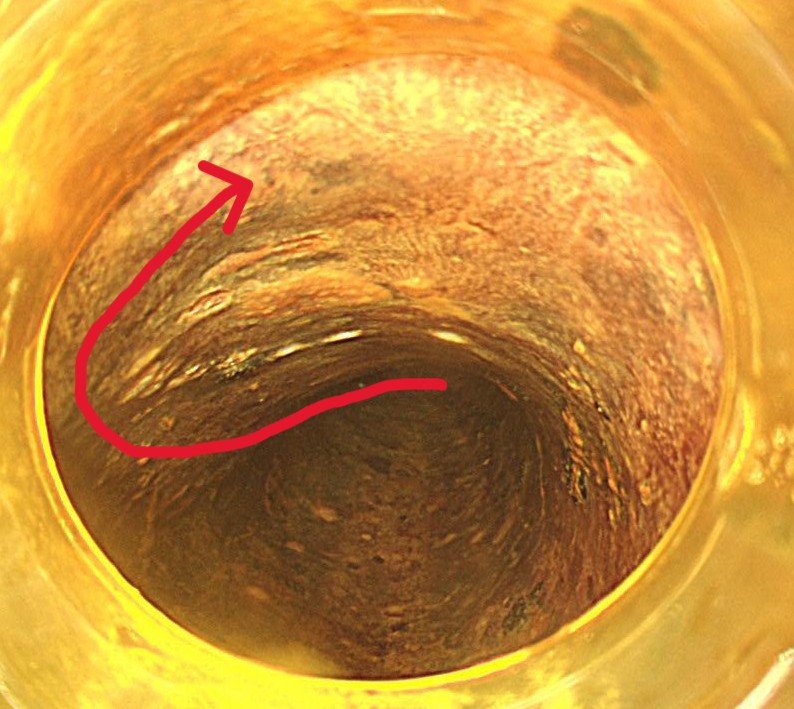

マーキング後にその外周に粘膜切開を行います。粘膜下局注はムコアップを使用し、デュアルナイフ1.5mmを用いてエンドカットモードで切開していきます。

粘膜下層剥離術を開始します。粘膜下局注はムコアップを使用しています。デュアルナイフ1.5mmでスイフトコアグ30で少しずつ剥離していきます。